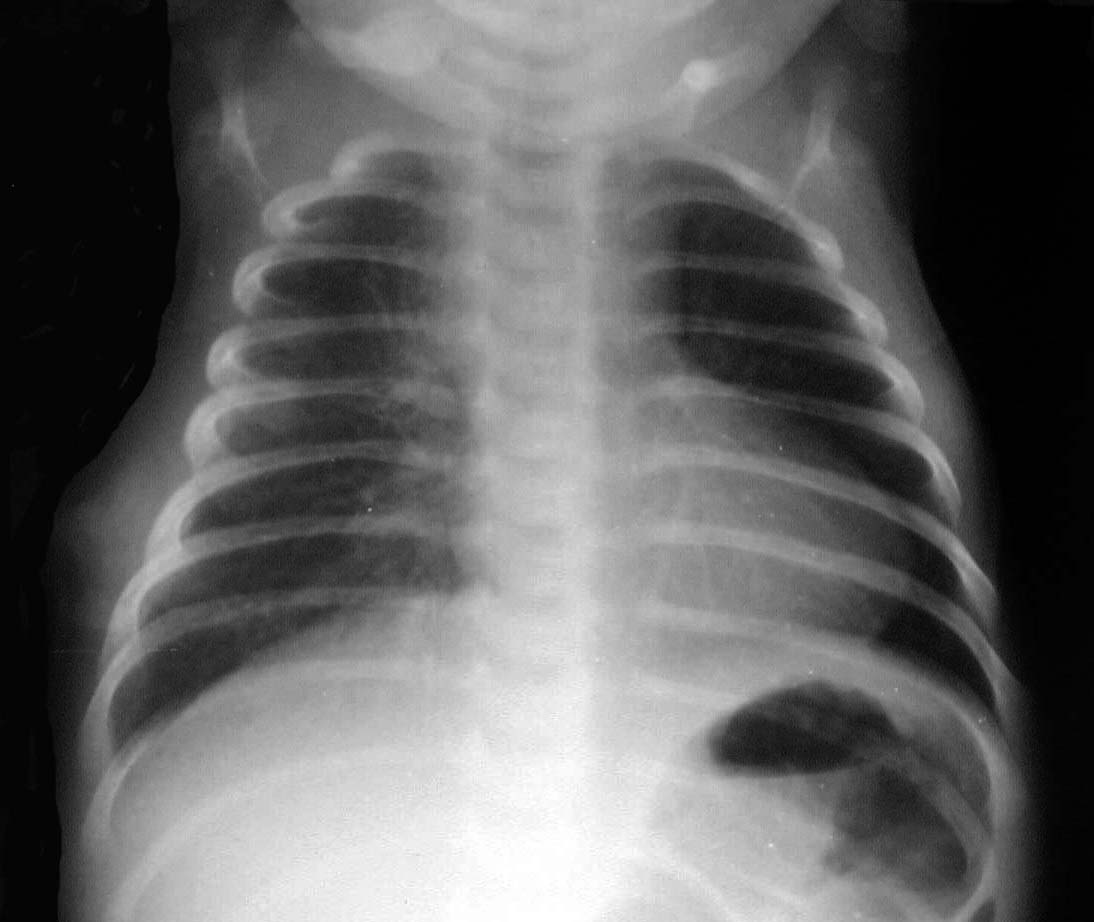

El aspecto de muñeco de nieve que adopta la silueta cardiaca en la proyección antero-posterior de tórax es característica del drenaje venoso pulmonar anómalo total. La porción inferior del muñeco corresponde al crecimiento de la aurícula y el ventrículo derechos, y la superior corresponde a la vena anómala que alcanza la vena cava superior.